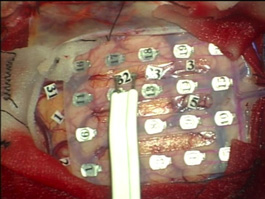

大脳マッピング Brain Mapping

脳の機能を微弱な電気刺激で調べます。運動機能を調べる場合は全身麻酔で手術を行うことが出来ます。

大脳皮質マッピング Cerebral cortex Mapping

大脳の表面の神経細胞の機能を調べます。運動野と呼ばれる体の動きを司る脳を見つけ出し、その部分を損傷しないように注意しながら手術を行います。

脳腫瘍を摘出する際に微弱な電気刺激でこれらの大切な神経線維を確認し、それを傷つけないようにします。当院では独自開発の電極により神経機能マッピングと摘出術を実現しました。

(左図)皮質下マッピング用電極 (NY Tract Finder)

(右図)NY Tract Finderによる神経線維刺激

(図)正確な脳マッピングにより機能を守り腫瘍摘出を行います。